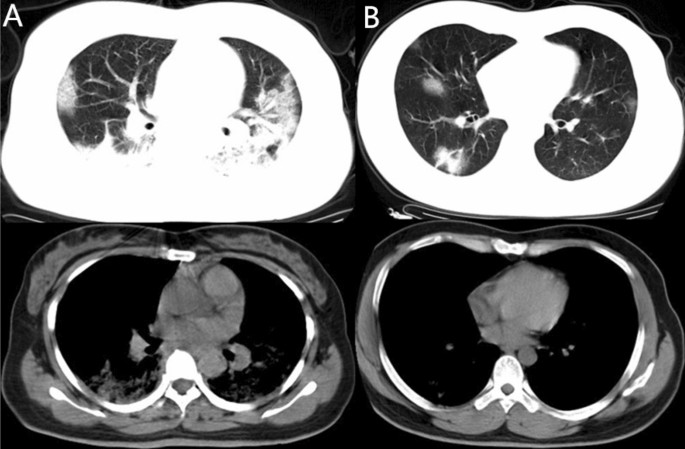

The demonstration of GGO components more than consolidation (Fig. 4) was higher in group 1 (24, 25.0%) than in group 2 (8, 10.5%), with a significant difference between the groups (p = 0.015). The demonstration of consolidation components more than GGO (Fig. 5) was higher in group 2 (54, 71.1%) than in group 1 (50, 52.1%) with significant difference (p = 0.012). The morphological features, including the presence of patchy shadowing (p = 0.286), and linear shadowing (p = 0.558) exhibited no significant difference between groups 1 and group 2.

Example of patients with CT demonstrated as consolidation > GGO component in Group 2. (A) 29-year-old female confirmed with COVID-19 pneumonia in Group 2 who had hospitalization days of 19 days. CT images demonstrated multiple lesions with mixed density which were predominantly solid components (arrows). (B) 28-year-old male in Group 2 with hospitalization days of 19 days. CT images also demonstrated multiple mixed density lesions with predominantly solid components (arrows).